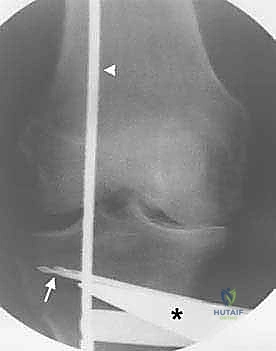

3. إجراء القطع العظمي (The Osteotomy):

باستخدام أدوات دقيقة ومناشير جراحية متطورة، يتم عمل قطع غير مكتمل في عظمة الساق. هناك طريقتان رئيسيتان:

* الشق المفتوح (Opening Wedge): يتم فتح العظم من الداخل وإضافة طعم عظمي (صناعي أو طبيعي) لملء الفراغ وتعديل الزاوية. وهي الطريقة الأكثر شيوعاً حالياً.

* الشق المغلق (Closing Wedge): يتم إزالة إسفين (مثلث) صغير من العظم من الجهة الخارجية وإغلاق الفراغ.

4. تعديل المحور:

يتم فتح العظم تدريجياً وببطء شديد حتى الوصول إلى الزاوية التي تم حسابها في التخطيط الرقمي قبل الجراحة.